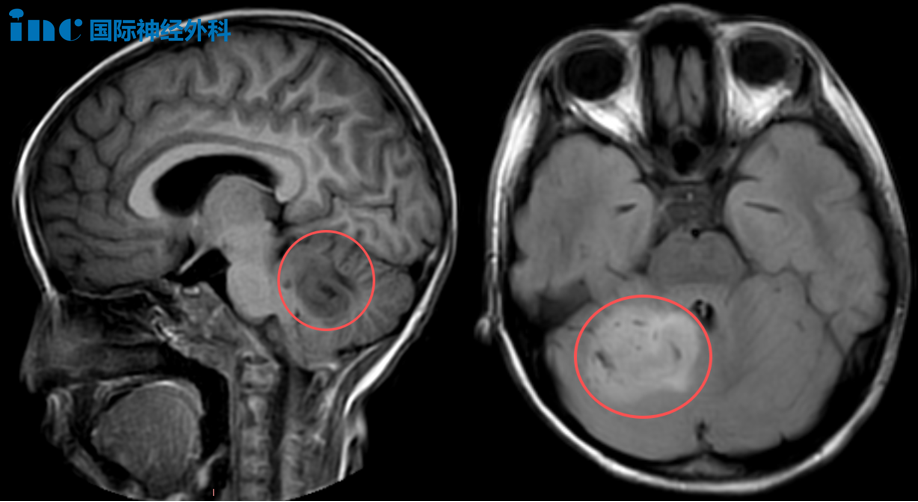

6岁女性小脑占位性病变患者

一名诊断为“小脑占位性病变”的女性患儿乐乐,3天内多次出现呕吐、头晕、恶心症状,父母情绪焦虑。最终咨询巴教授后,家长决定手术,关键因素为面对面交流时巴教授明确表示:“该肿瘤可以手术。”